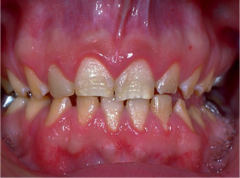

NUG

-Borrelia vincentii plus fusiform bacillus -painful, erythematous gingivitis w/ necrosis and cratering of the interdental papillae, foul odor and metallic taste possible fever and lymphadenopathy